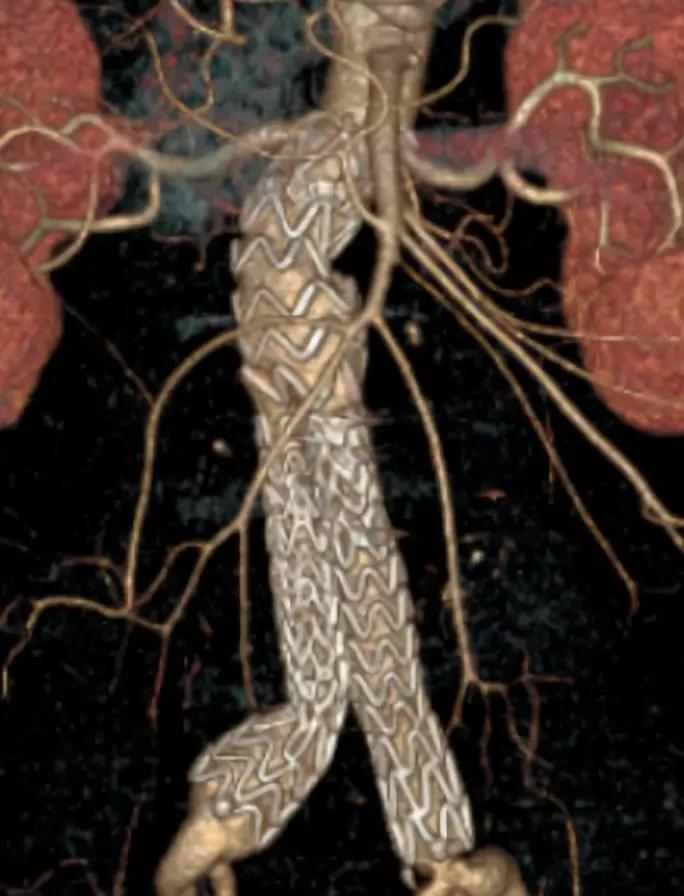

此次研究,纳入腹主动脉瘤的最大直径为85mm,平均直径为50.78mm;最短瘤颈长度为11mm,平均长度为31.34mm;最大肾下成角为74.6度,平均角度为32.48度。从动脉瘤最大直径变化来看,经过腹主动脉腔内治疗后,在出院前和术后6个月都有所减小。 在此次研究中,彩神在线网信彩票-彩神通免费版下载-彩神8争霸vlll-彩神购彩购彩大厅-彩神软件陆立根免费版-彩神ll争霸3-彩神ll彩神8-彩神ll争霸彩票-拼搏在线彩神网网页版Yuranos™新一代腹主动脉覆膜支架系统临床试验初步展现了优秀的临床试验结果,其30天内MAE发生率低,安全性得以验证;而且由于该产品的柔顺性有较大提升,输送器直径减小,对于短瘤颈和角度大的病例是更好的选择。 入组病例展示: 病例一:男性,年龄69岁,既往高血压,糖尿病病史。术前腹主动脉瘤直径67.3mm,近端瘤颈长度23.2mm,近端锚定区直径21.2mm,肾下成角60.5度。 术中从右侧股动脉穿刺,选用彩神在线网信彩票-彩神通免费版下载-彩神8争霸vlll-彩神购彩购彩大厅-彩神软件陆立根免费版-彩神ll争霸3-彩神ll彩神8-彩神ll争霸彩票-拼搏在线彩神网网页版型号为AB-2412-50-120的主体支架,支架近端定位于右肾动脉开口处,后释放打开裸支架,并向下释放主体短分支,左侧输送进入彩神在线网信彩票-彩神通免费版下载-彩神8争霸vlll-彩神购彩购彩大厅-彩神软件陆立根免费版-彩神ll争霸3-彩神ll彩神8-彩神ll争霸彩票-拼搏在线彩神网网页版髂动脉延长支架IE-1416-100,并释放,保留左侧髂内动脉。接着释放主体长分支,右侧输送进入彩神在线网信彩票-彩神通免费版下载-彩神8争霸vlll-彩神购彩购彩大厅-彩神软件陆立根免费版-彩神ll争霸3-彩神ll彩神8-彩神ll争霸彩票-拼搏在线彩神网网页版髂动脉延长支架IE-1424-80,并释放,保留右侧髂内动脉。 手术顺利,无内漏,持续时间1小时10分钟。术后CTA检查,支架形态良好,无内漏。详见下图: 术前影像 术中影像 出院前影像 术后6个月影像 术后1年影像 病例二:女性,年龄72岁,既往高血压,静脉曲张病史。术前腹主动脉瘤直径48.81mm,近端瘤颈长度16.15mm,近端锚定区直径18.43mm,肾下成角66度。 术中从右侧股动脉穿刺,选用彩神在线网信彩票-彩神通免费版下载-彩神8争霸vlll-彩神购彩购彩大厅-彩神软件陆立根免费版-彩神ll争霸3-彩神ll彩神8-彩神ll争霸彩票-拼搏在线彩神网网页版型号为AB-2412-50-140的主体支架,支架近端定位于右肾动脉开口处,后释放打开裸支架,并向下释放主体短分支,左侧输送进入彩神在线网信彩票-彩神通免费版下载-彩神8争霸vlll-彩神购彩购彩大厅-彩神软件陆立根免费版-彩神ll争霸3-彩神ll彩神8-彩神ll争霸彩票-拼搏在线彩神网网页版髂动脉延长支架IE-1414-120,并释放,保留左侧髂内动脉。接着释放主体长分支,右侧输送进入彩神在线网信彩票-彩神通免费版下载-彩神8争霸vlll-彩神购彩购彩大厅-彩神软件陆立根免费版-彩神ll争霸3-彩神ll彩神8-彩神ll争霸彩票-拼搏在线彩神网网页版髂动脉延长支架IE-1414-80,并释放,保留右侧髂内动脉。